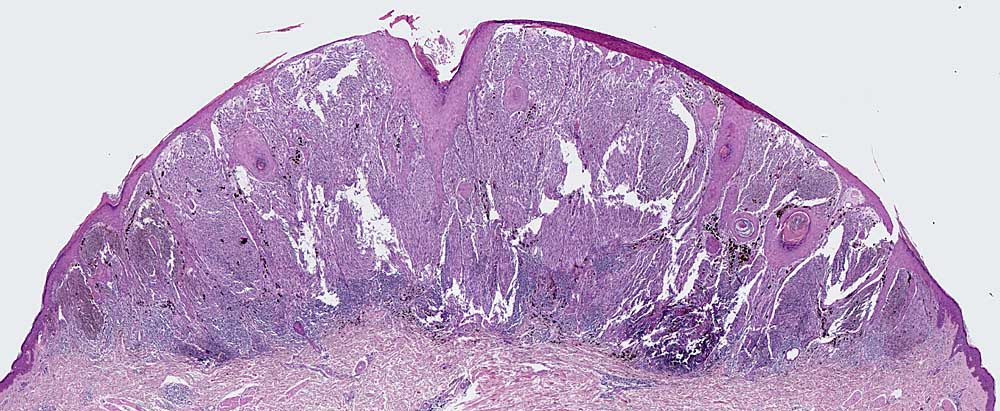

PathoPic – image database / PathoPic ID 6720 - spitzoides Melanom

spitzoides Melanom

Auffallend symmetrischer Tumor aus spindeligen Tumorzellen. Auf den ersten Blick erinnert die Läsion an einen Spitz Naevus. Die Pigmentverteilung ist jedoch asymmetrisch, die Tumorzellen bilden sehr zellreiche expansive Faszikel ohne dazwischenliegendes Stroma, die Epidermis ist fokal verdünnt.

Nachweis zahlreicher Mitosen